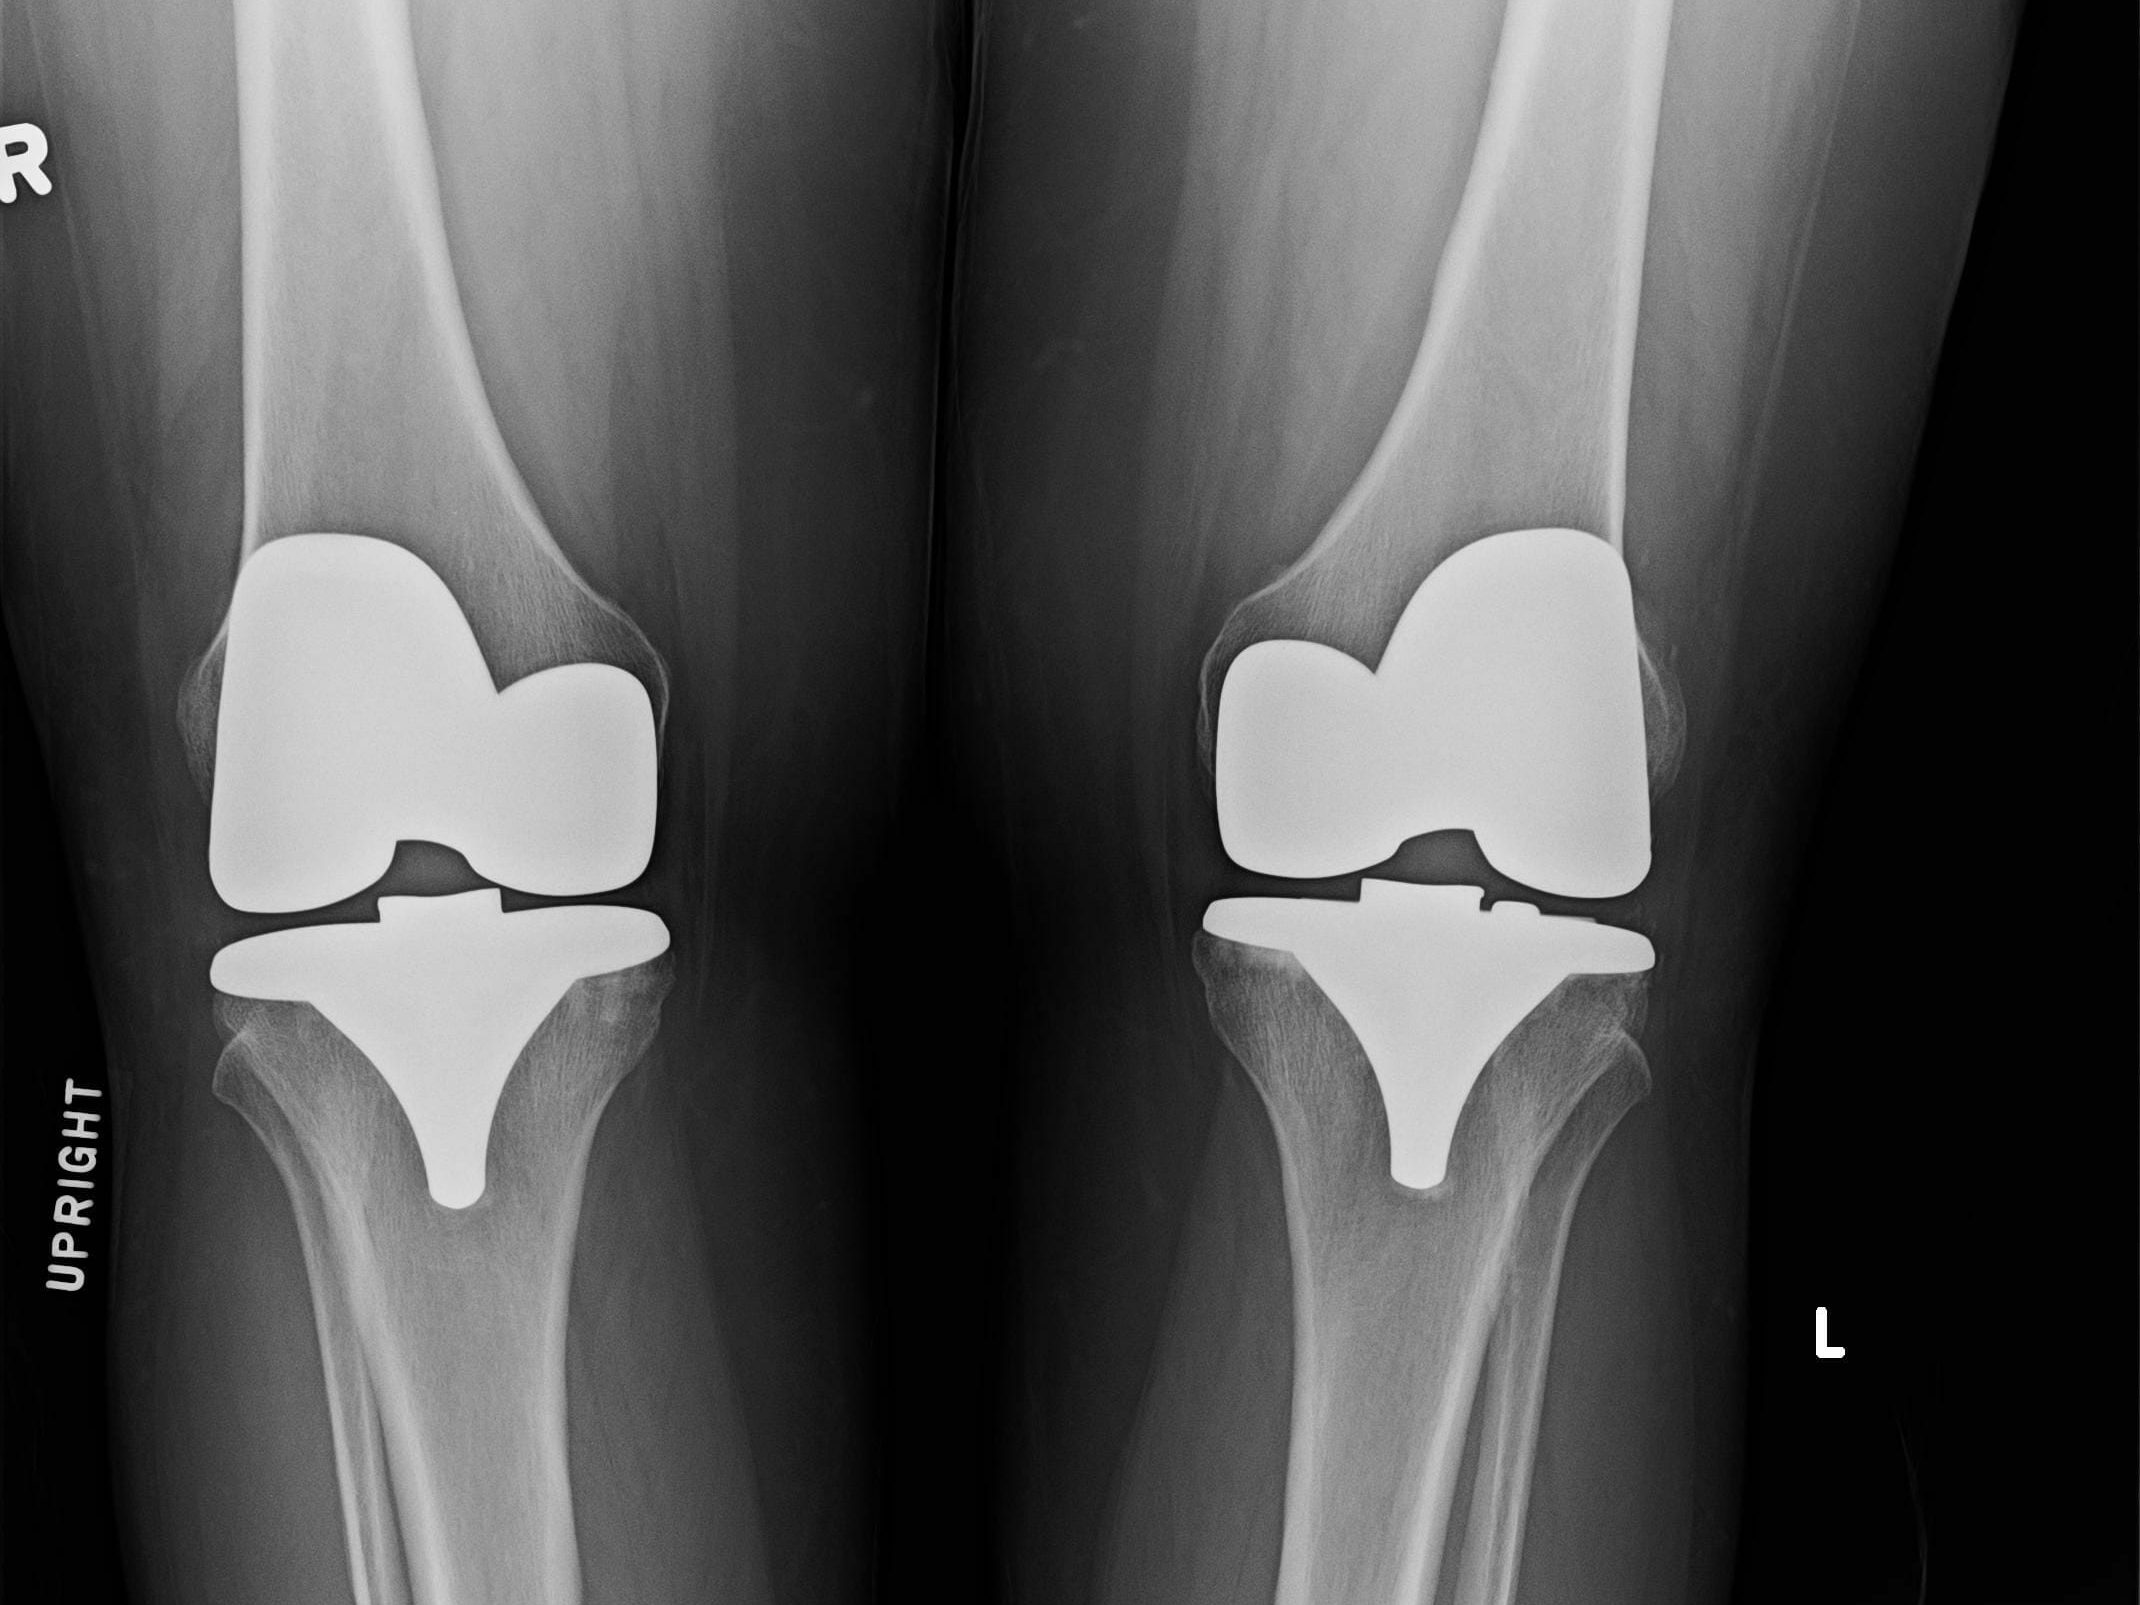

PJ Ewing discusses knee surgery and recovery, particularly total knee replacement, emphasizing self-advocacy in navigating the medical system. He explores challenges post-surgery, alternative recovery methods, and the X10 knee recovery system’s benefits. PJ highlights rehab complexities, factors impacting surgery success, misconceptions around recovery for healthier individuals, and the importance of personalized physical therapy for effective recovery strategies. He advises on steady rehabilitation, avoiding excess force, and pain. PJ addresses common post-surgery difficulties, offering practical advice and emphasizing self-advocacy for successful recovery outcomes.

In this interview with PJ Ewing, he shares his expertise in knee surgery and recovery, focusing on total knee replacement. He emphasizes the importance of advocating for oneself in the medical system, especially when dealing with challenges post-surgery. PJ discusses the common issues faced by individuals preparing for or recovering from knee replacement surgery and highlights the significance of finding alternative approaches to traditional recovery methods.

PJ delves into the complexities of rehab and recovery, pointing out how factors like age, gender, weight, range of motion, and scar tissue can impact the success of knee surgery. He introduces the X10 knee recovery system, a cloud-connected device designed to assist individuals in their recovery process by providing gentle yet relentless exercises to improve bending and straightening without causing pain, swelling, or scar tissue.

The conversation touches on the misconceptions around recovery for healthier and younger individuals, revealing how they can face more challenges due to their body’s efficient healing responses. PJ stresses the importance of a steady and frequent approach to rehabilitation, avoiding excess force and pain in the process. He also discusses the role of physical therapy clinics, emphasizing the need for personalized and effective recovery strategies tailored to each individual’s unique needs.